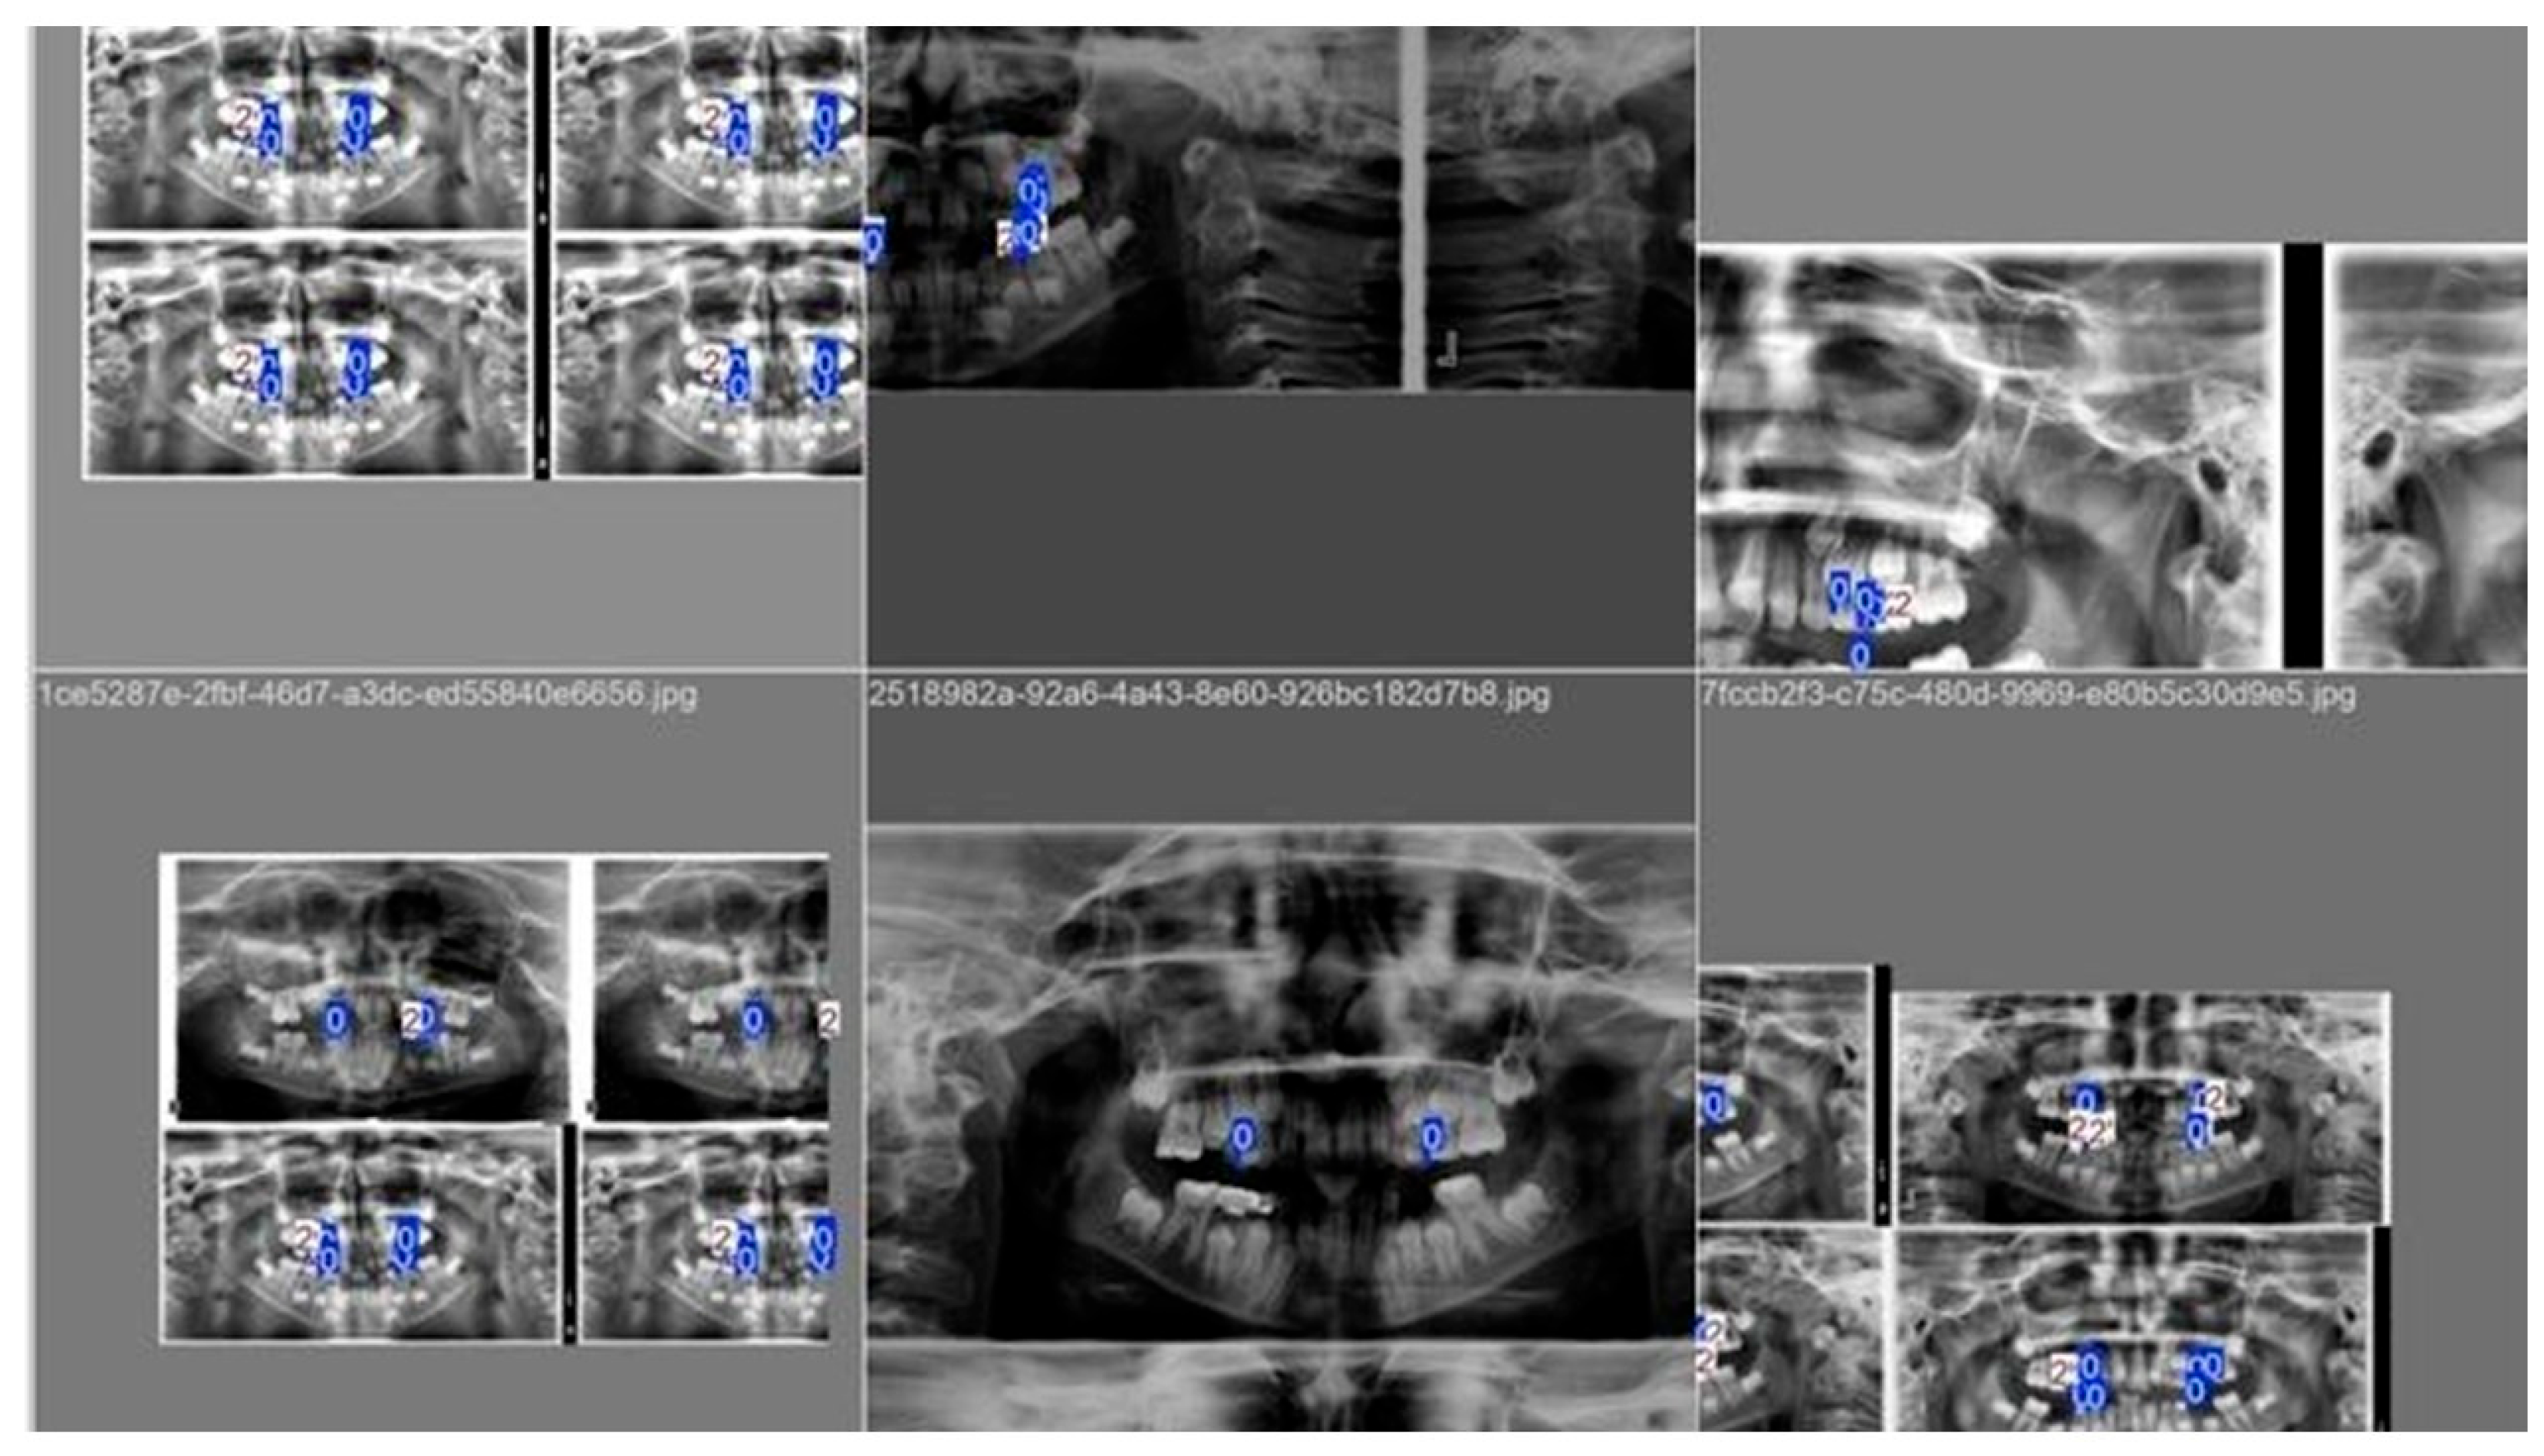

1. Introduction

2.2. Study Population and Image Acquisition

2.3. Dataset Composition and Splitting

2.4. Image Preprocessing

2.5. Caries Annotation and Ground Truth Definition

2.7. Deep Learning Model Architecture and Training